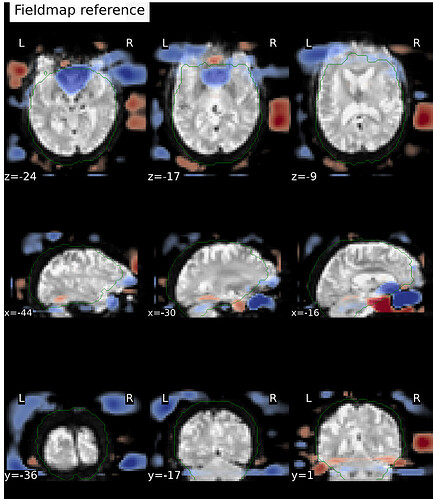

I’ve run fMRIprep 24.1.0 on ~ 150 datasets (PE-dir: func/RL_bold;fmap/LR_epi), and I noticed that for one of the subjects, the EPI and the reference fieldmap are not aligned well with each other.

Which appears as a signal-void region, affecting LR_epi (one top) and RL_bold (two bottom) differently: